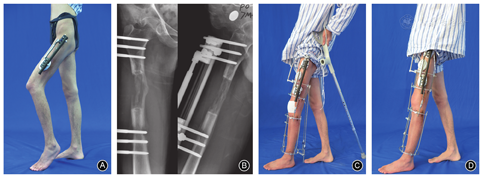

实施胫骨近端截骨延长术,随着胫骨长度的增加,跨越膝、踝关节的腓肠肌、踝后肌腱、筋膜等的张力也随之增加,从而引起不同程度的屈膝畸形、足下垂和足趾的屈曲挛缩等。股骨延长时增加大腿肌肉尤其是股四头肌和髂胫束的张力,引起膝关节挛缩畸形,如膝并节僵硬、伸直受限、屈曲、小腿外旋等[17](图2);股骨大幅度延长还可发生髋关节屈曲、外展挛缩及关节僵硬等。

如果软组织挛缩畸形较轻,经过加强正确的功能锻炼后一般可恢复[18]。儿童的膝关节僵硬训练时要循序渐进,避免损伤骺板。对于康复锻炼效果不佳的挛缩畸形,则需要通过外固定或辅具牵伸纠正(图2),必要时行挛缩肌腱松解术[19]。为有效维持大幅度肢体延长时骨关节与软组织之间的动态平衡,凡股骨或胫骨计划延长>4 cm者,应常规行跨关节穿针并安装同步弹性延长器[20,21]。